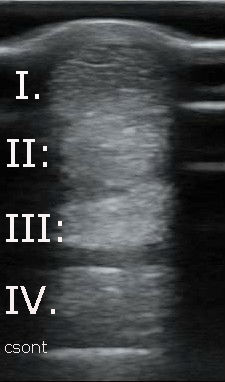

Az első képen hosszmetszetben láthatóak az inak. Rostjaik szabályosan lefutó erős, fehér csíkok. A második képen keresztmetszetben láthatóak az inak. Rostjaik erős, fehér pöttyök. A négy ín fentről lefelé: I. Felületes ujjhajlító ín. I.: Mély ujjhajlító ín. III. Járulékos szalag. IV. Egyenítő szalag (Suspensory ligament)